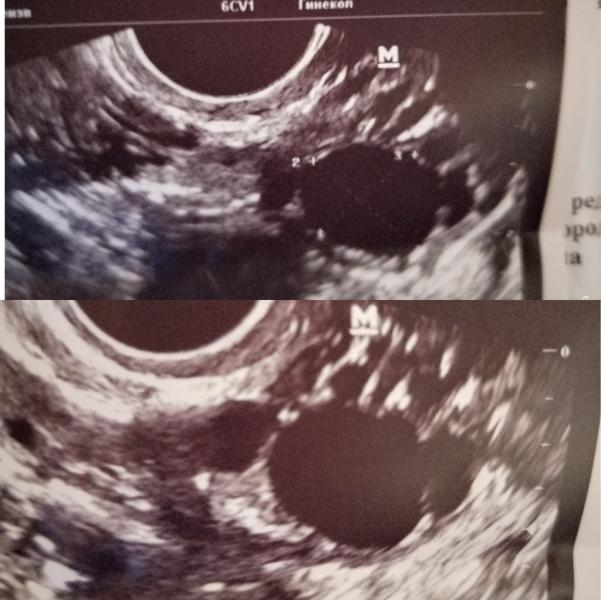

Девушки, добрый вечер🌼Сходила я на узи на 6дц и, вроде, всё не плохо, но есть вопросы)))

1) что такое дф с перегородкой(на фото)?

Фолликул с перегородкой, возможно 2 фолликула доминантные созрели слишком рядом друг другом, по этому и кажется как будто с перегородкой